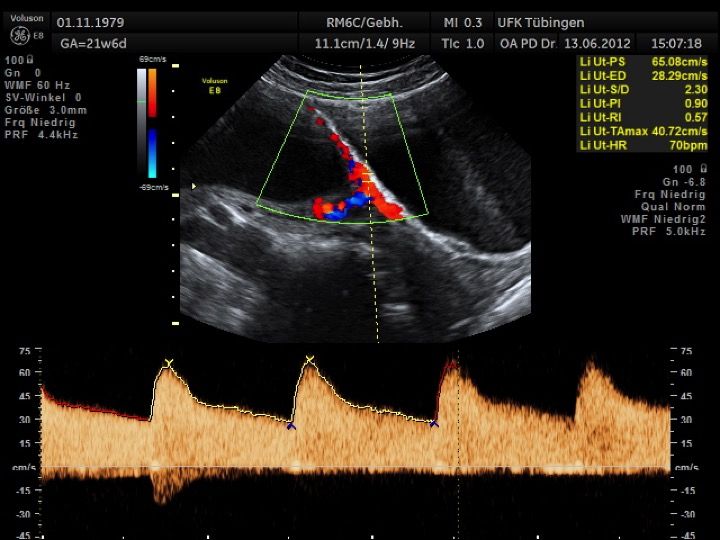

Die Präeklampsie ist eine relativ häufige Komplikation in der Schwangerschaft und betrifft die Schwangere selbst. Sie tritt in der zweiten Hälfte der Schwangerschaft auf und beinhaltet eine Bluthochdruckproblematik, eine vermehrte Eiweißausscheidung im Urin und Wassereinlagerungen. Zahlreiche andere Probleme können mit der Präeklampsie einhergehen. Häufig kommt es zu einer fetalen Wachstumsretardierung.

Mithilfe des Ersttrimester-Screenings kann das persönliche Risiko einer Präeklampsie bestimmt werden. Dazu wird die Vorgeschichte der Schwangeren, der aktuelle Blutdruck, das Ergebnis der Ultraschalluntersuchung (Widerstand in den Gebärmutter-nahen Gefäßen) und der Blutabnahme bei Ihnen (PAPP-A) kombiniert. Sollte das Risiko über 1:100 sein, empfehlen wir die tägliche Einnahme von Aspirin 150mg bis zu 35.SSW und eine gezielte Überwachung der weiteren Schwangerschaft.

Auch hier gilt wieder, dass der Untersuchung eine Aufklärung und Beratung vorausgeht und die Ergebnisse nach Abschluss der Untersuchung ausführlich besprochen werden.